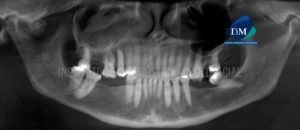

Paciente de sexo masculino de 32 años de edad acude al Instituto de Diagnóstico Maxilofacial para evaluación de la pieza 31 por motivo de colocación